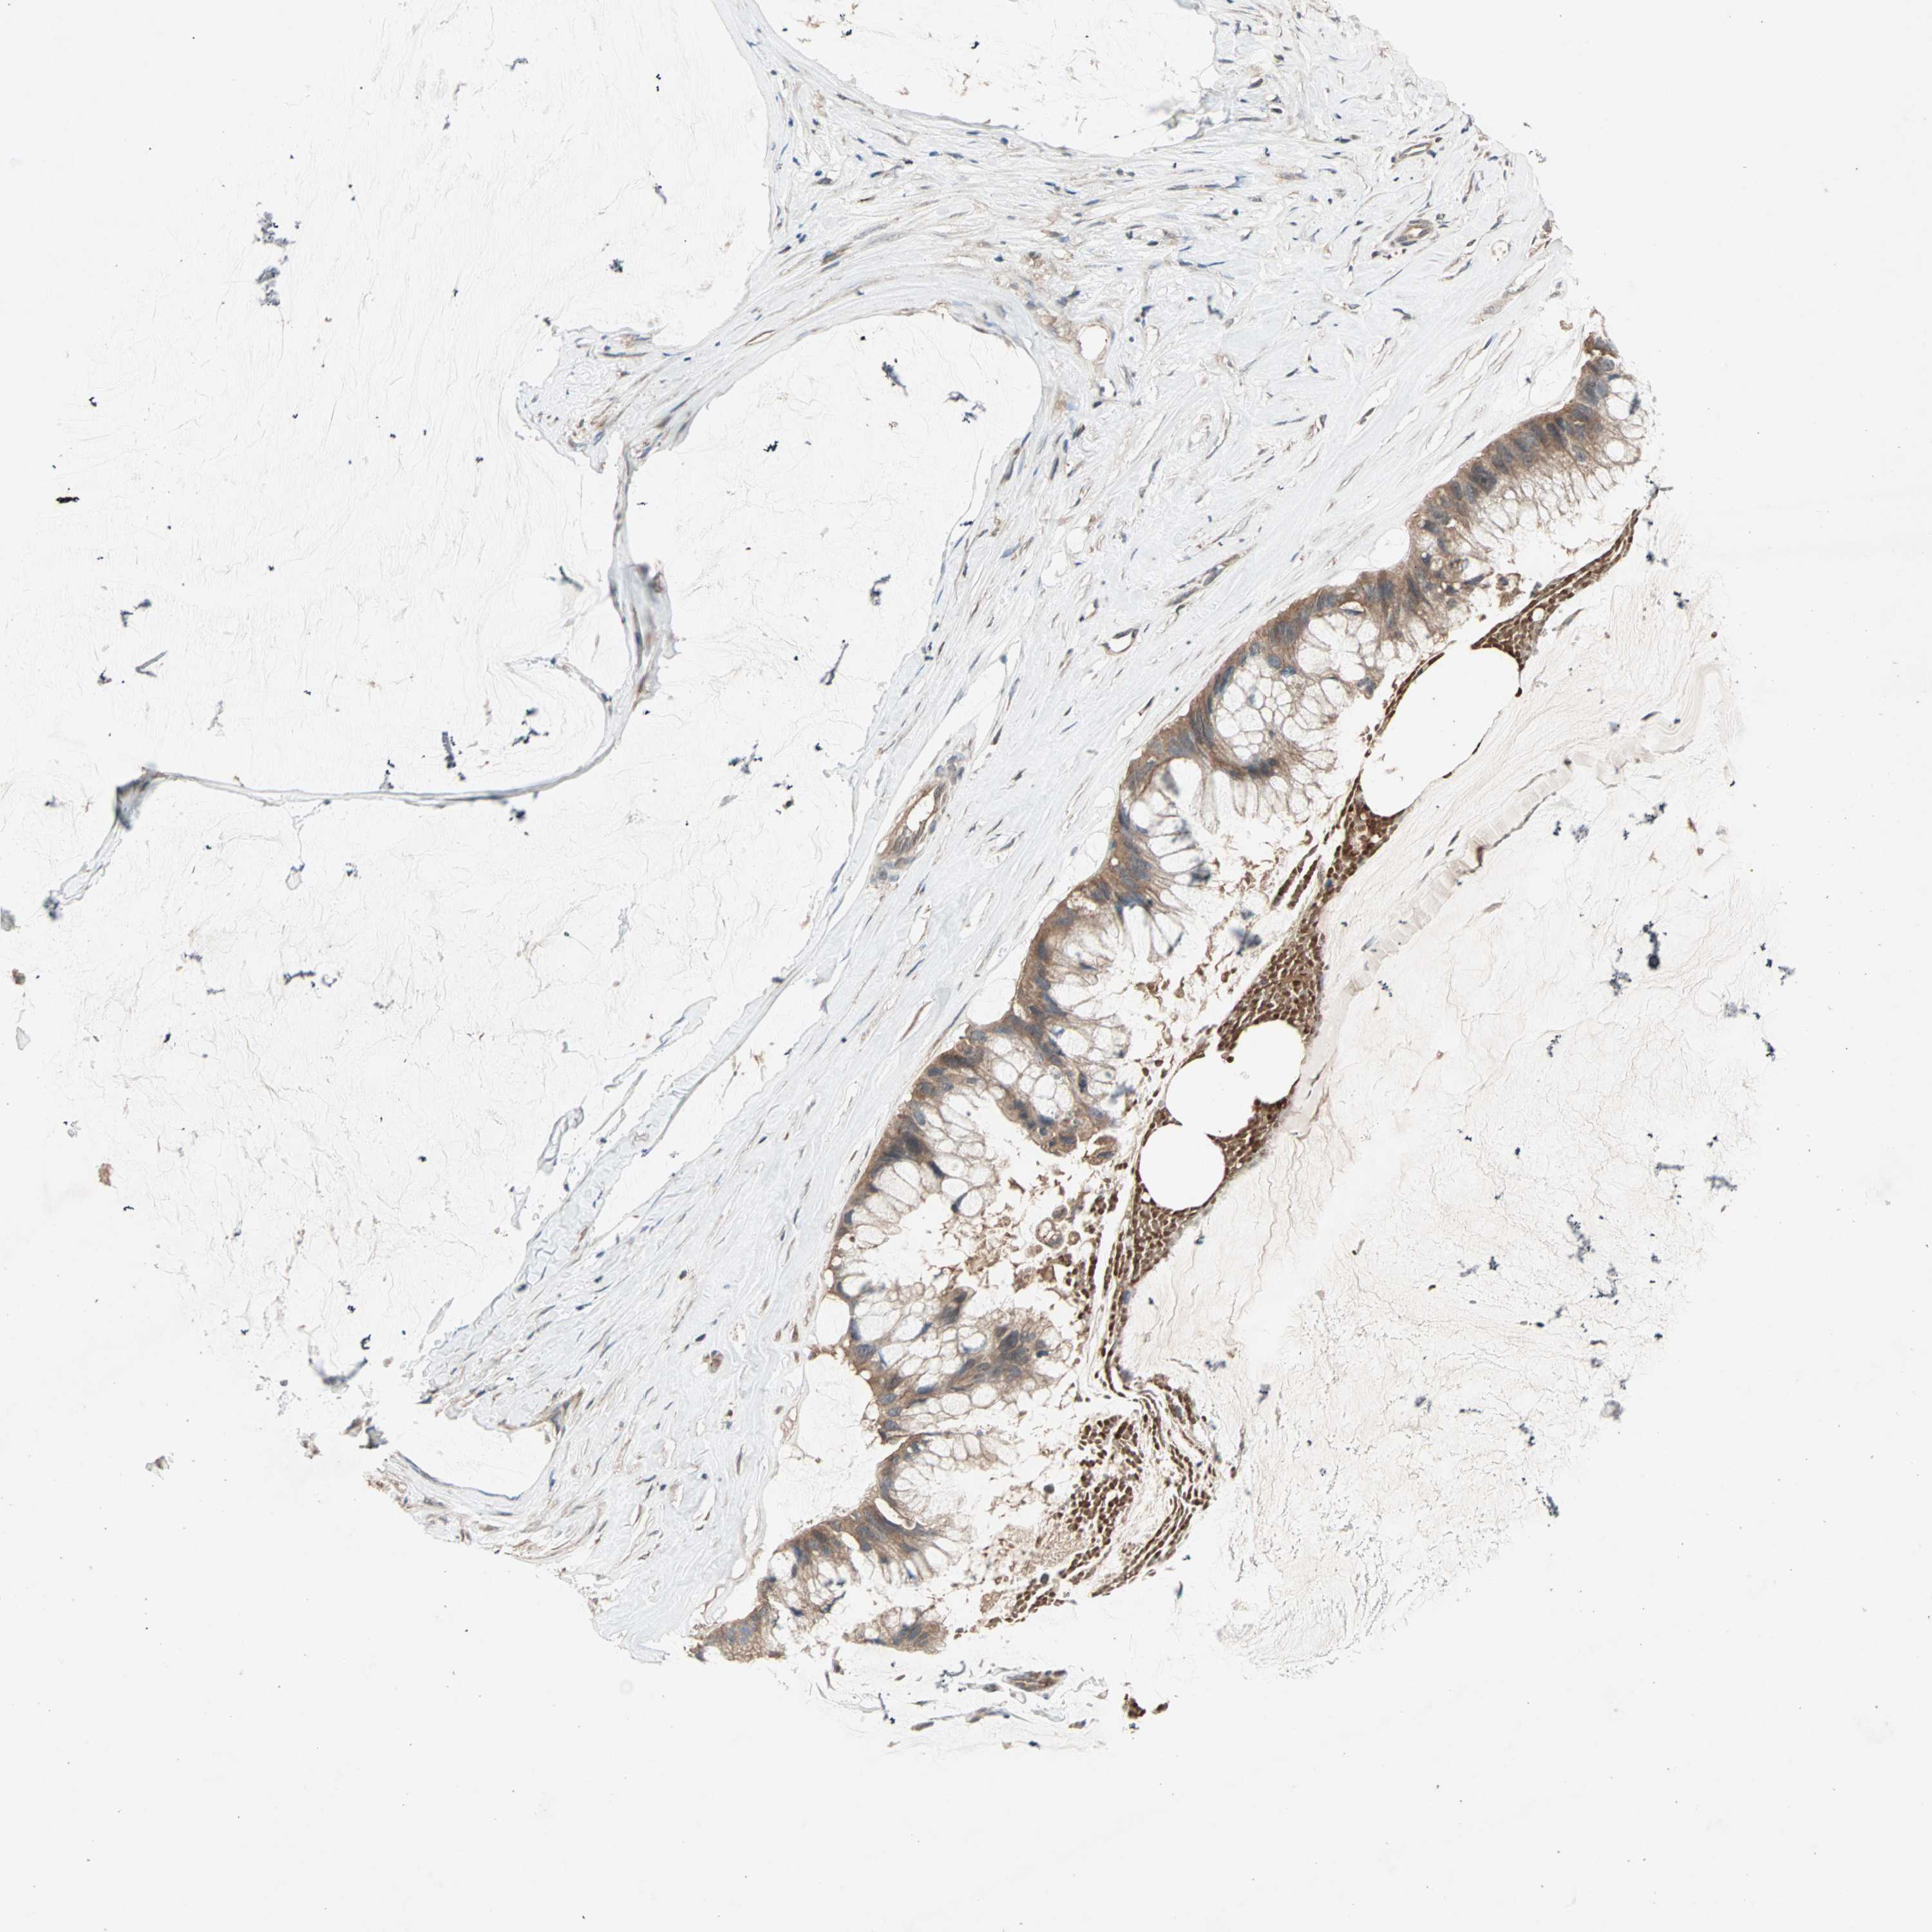

OVARIAN CANCER - Protein expressioni

A mouse-over function shows sample information and annotation data. Click on an image to view it in a full screen mode. Samples can be filtered based on level of antibody staining by selecting one or several of the following categories: high, medium, low and not detected. The assay and annotation is described here.

Note that samples used for immunohistochemistry by the Human Protein Atlas do not correspond to samples in the TCGA dataset.

Antibody stainingi

Antibody staining in the annotated cell types in the current human tissue is reported as not detected, low, medium, or high, based on conventional immunohistochemistry profiling in selected tissues. This score is based on the combination of the staining intensity and fraction of stained cells.

Each image is clickable and will lead to virtual microscopy that enables deeper exploration of all samples and also displays staining intensity scores, fraction scores and subcellular localization as well as patient and tissue information for each sample.

Antibody HPA005651

Staining

High

Medium

Low

Not detected

Intensity

Strong

Moderate

Weak

Negative

Quantity

>75%

75%-25%

<25%

None

Location

Nuclear

Cytoplasmic/membranous

Cytoplasmic/membranous,nuclear

Cystadenocarcinoma, serous, NOS

Carcinoma, endometroid

Cystadenocarcinoma, mucinous, NOS

Carcinoma, NOS